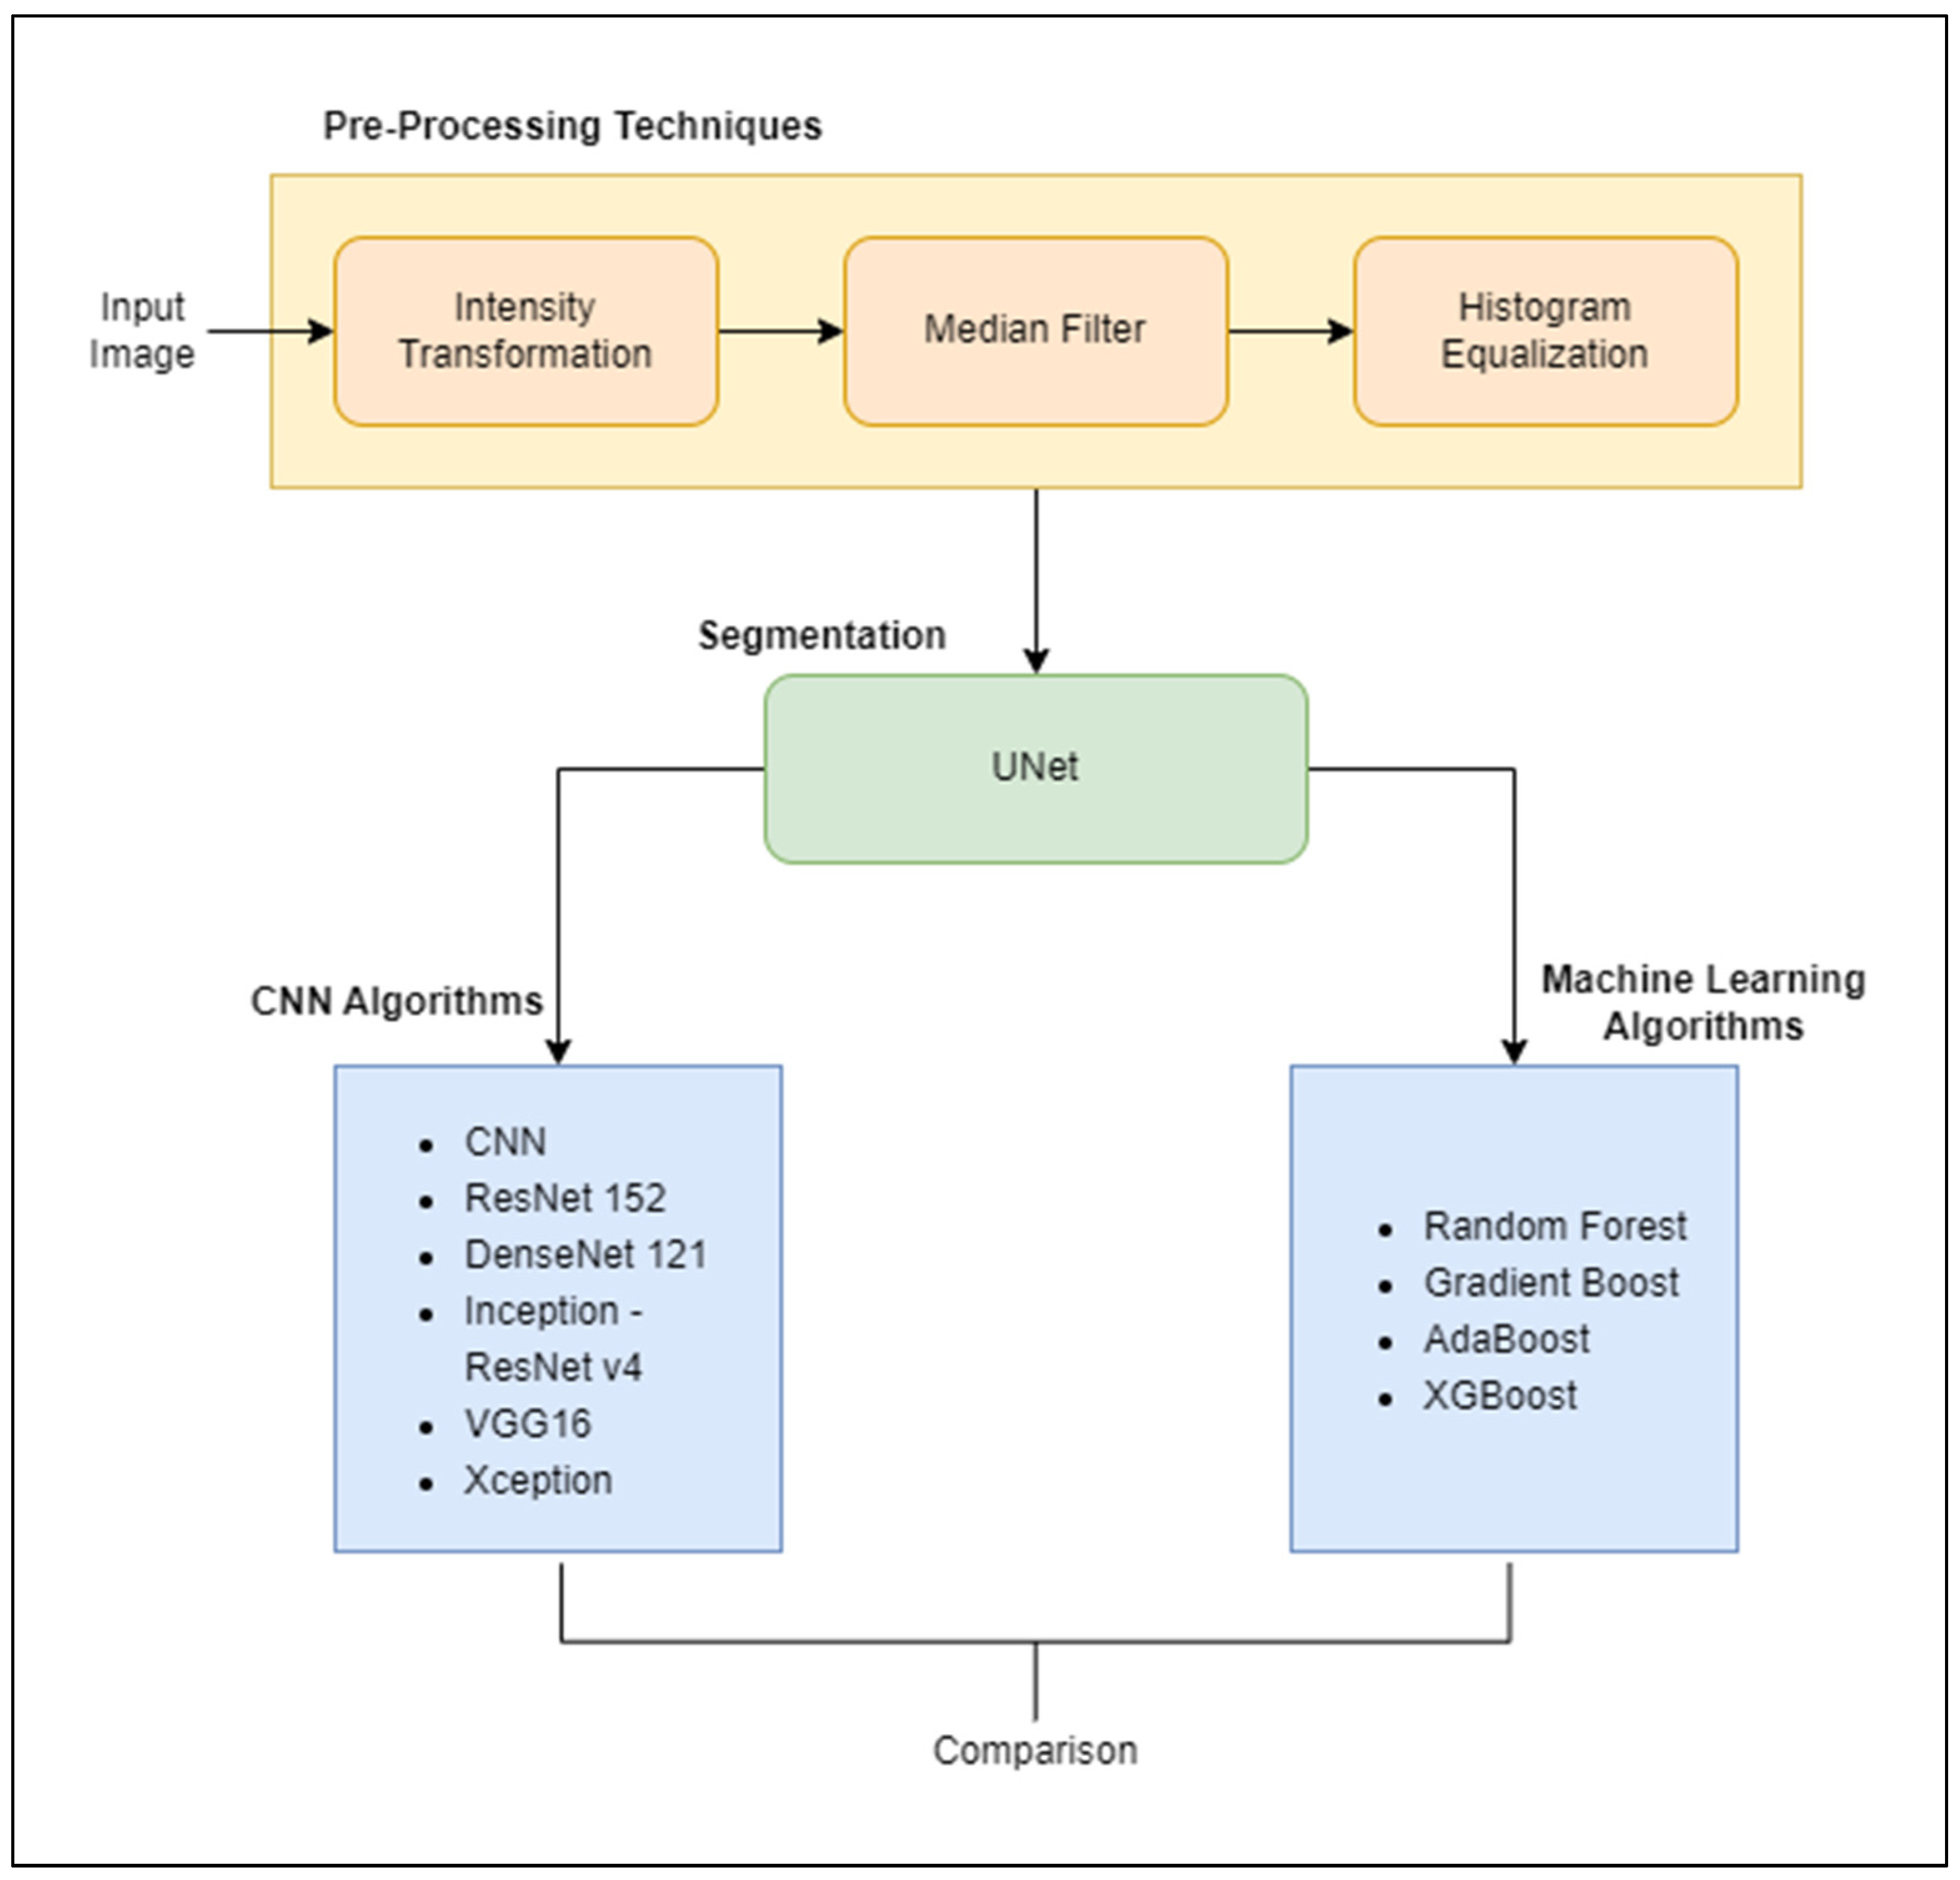

3. Methodology

3.3. Detailed Methodology